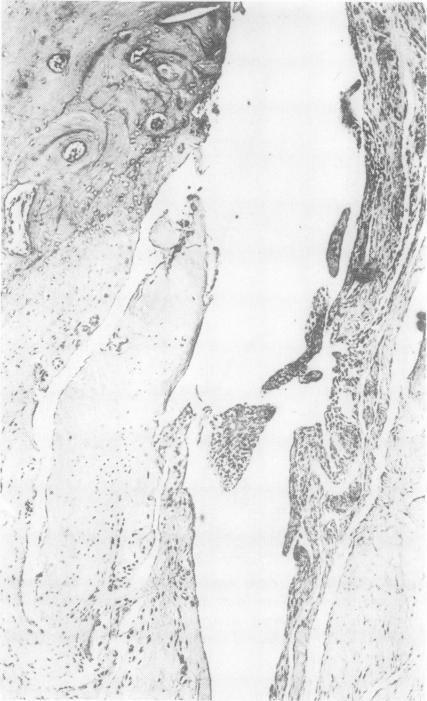

Effects of prednisolone in an experimental model of arthritis in the rabbit.

Ann Rheum Dis. 1971 Sep;30(5):509-21. doi: 10.1136/ard.30.5.509.